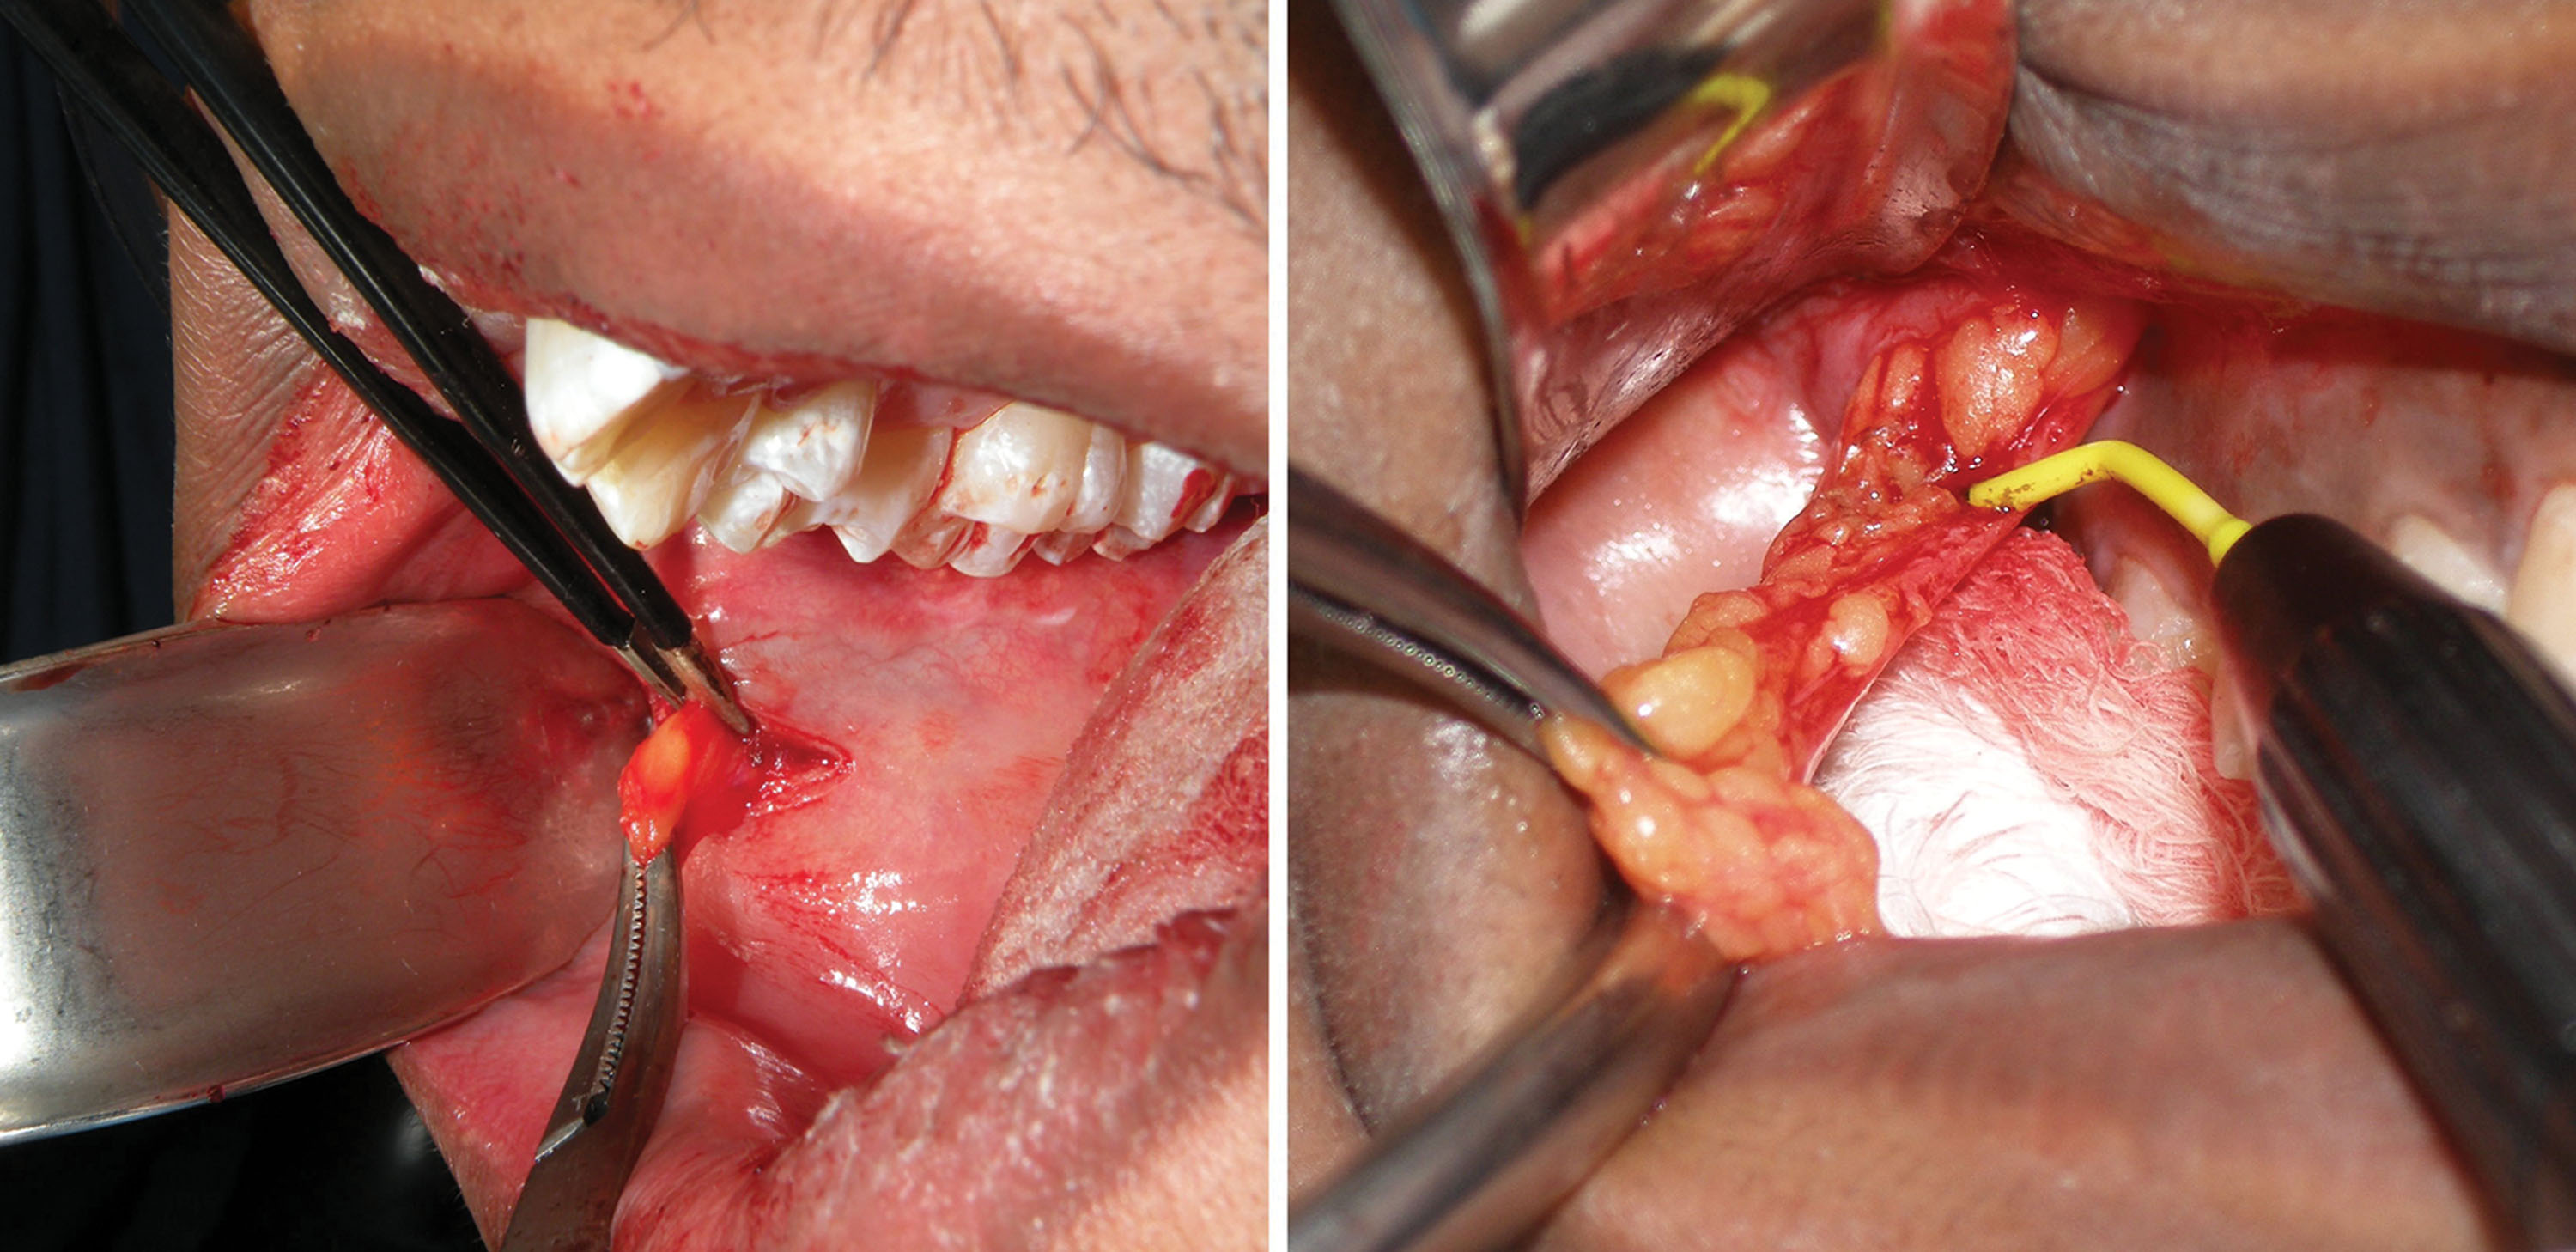

If the fat does not present itself, the hemostat is repositioned superolaterally, and spreading is continued. If the fat pad mass is still not located, a 3- to 4-mm suction tip can be inserted while the assistant pinches the suction hose. The suction is then directed superolaterally, and the hose is unpinched to activate the suction. This maneuver will frequently engage the fat pad and pull it from the incision ( Fig. 15.17 ). Once secured, the buccal pad may present in various configurations in given patients ( Fig. 15.18 ).

Once the available fat is delivered into the oral cavity, it is reduced with bipolar forceps or an electrosurgery tip at the base for coagulation ( Fig. 15.21 ). It is important to use a coagulative modality as vessels penetrate the fat pad in the same manner as blepharoplasty.